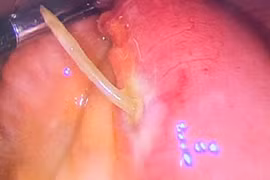

(khoahocdoisong.vn) - Nạn nhân lần này là bé trai, 6 tuổi được chuyển viện từ tuyến dưới với biểu hiện đau bụng 3 ngày, ói nhiều, không đi cầu được kèm bụng trướng hơi, sốt.

Dị vật nam châm trong đường tiêu hóa là tai nạn rất nguy hiểm. Khi các viên nam châm đi vào đường ruột, các cực trái dấu sẽ hít nhau gây tổn thương niêm mạc, thủng ruột dẫn tới nhiễm trùng đe dọa tính mạng của trẻ.